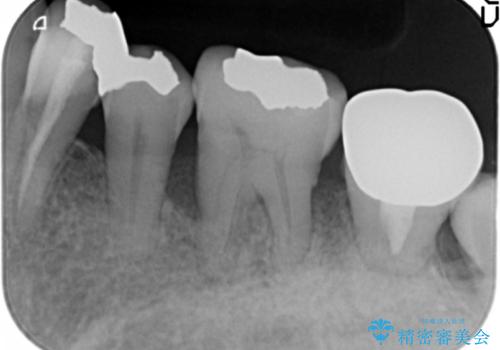

- 全顎的な重度歯周病の患者様です。

骨吸収の進行している左下臼歯部に、再生療法(骨を増やす手術))を行いました。

埋伏していた親知らず、保存不可能な左下の一番奥の歯(左下7)は抜歯しました。